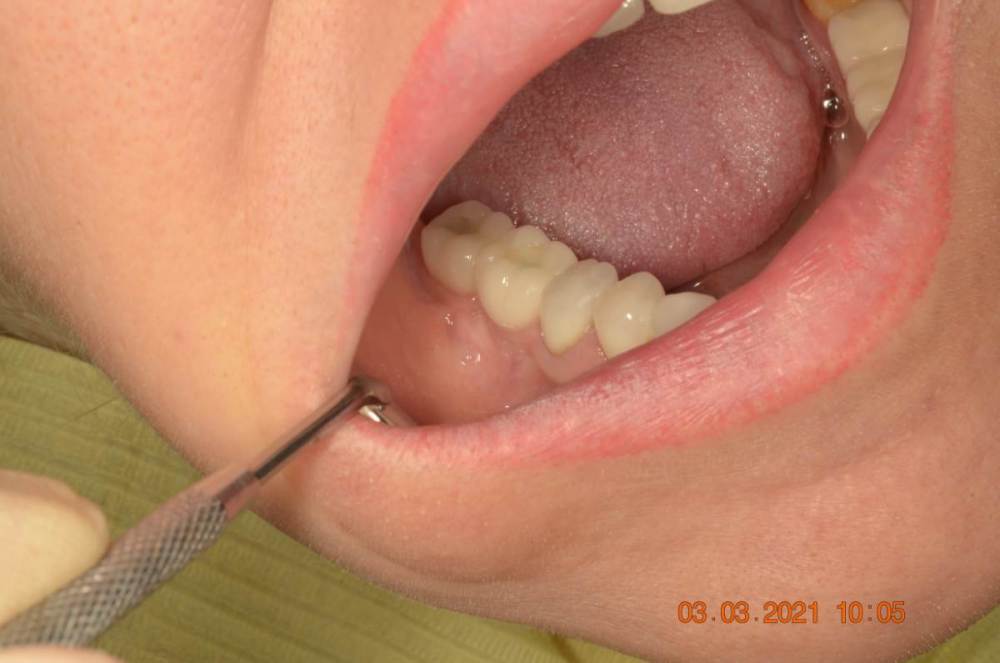

Большой Зеленый Опубликовано 7 ноября, 2022 Поделиться Опубликовано 7 ноября, 2022 Обратите внимание на даты 2 Ссылка на комментарий